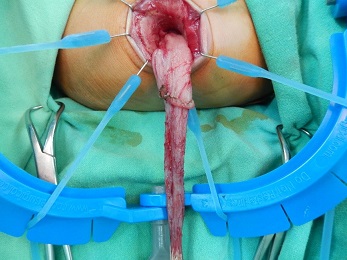

【112-2 醫學(五) 第49題】承上題,診斷確定後,即將無神經節的腸段切除,再將有神經節的腸段拉下(如圖),與遠端肛門口做端對端接合,是下列何種術式?

詳解

破題關鍵

這題的關鍵在於辨識 Hirschsprung's disease (先天性巨結腸症) 的經典術式描述:「切除無神經節腸段,將有神經節腸段拉下,與肛門口端對端接合」。圖片顯示的是手術中將腸道拉出肛門口的畫面,符合此類手術。

選項拆解